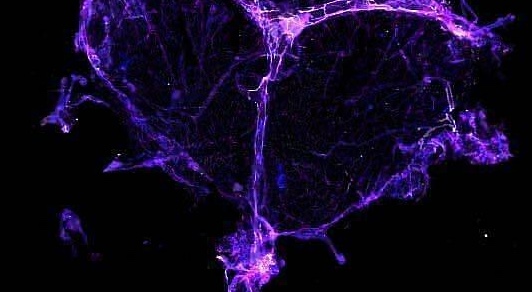

«Хіміомозок» може бути наслідком пошкодження дренажної системи мозку

«Хіміомозок» може бути наслідком пошкодження дренажної системи мозку